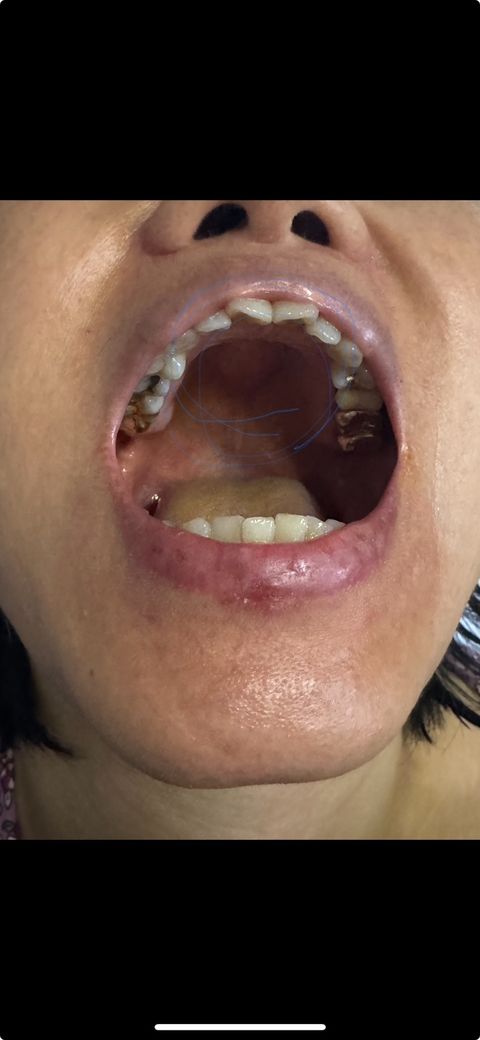

입천장 부음 혹 구강암이늘까봐… 걱정

입천장에 뭐가 난지 1달정도 됐는데 격정되서 사진 찍고 올려요 전문가분들 사진 보고 말해주세요 ㅠㅠㅠㅠㅠㅠㅠㅠㅠㅠㅠㅠㅠㅠㅠ

사진으로 보기에는 입천장뼈가 증식한 것으로 보입니다. 그래도 치과에서 진단 받아보시는 게 좋겟습니다.

입천장에 생긴건 큰 문제가 잇는건 아니고, 입천장에 잇는 뼈라고 생각하시면될것같습니다.

사진으로 봤을 경우에는 외골증으로 보입니다. 외골증은 치조골이 밖으로 자라나온 것으로 크게 문제를 발생시키거나 그러지는 않습니다. 자세한 확인을 위해서 치과에서 진료를 받아보는 것을 권유 드립니다.